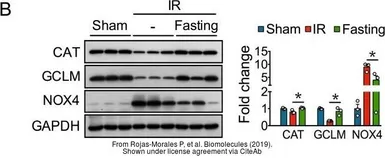

The data was published in the journal Biomolecules in 2019. PMID: 31505885